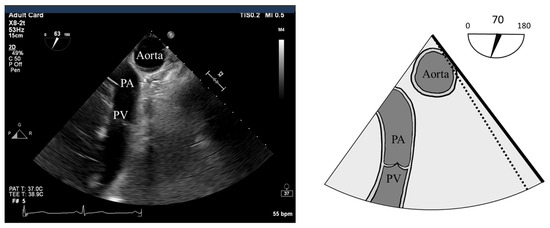

- S’: Measured from a non-standard TEE view. In the Deep Transgastric long axis (DTG-LAX) view, omniplane to 120–150° and turn right. The RV and lateral tricuspid annulus will be centered on the screen. Tissue Doppler Imaging (TDI) is then used to measure the systolic velocity of the lateral tricuspid valve annulus (S’) with >10 cm/s considered normal [79] (Figure 4 and Figure 5).